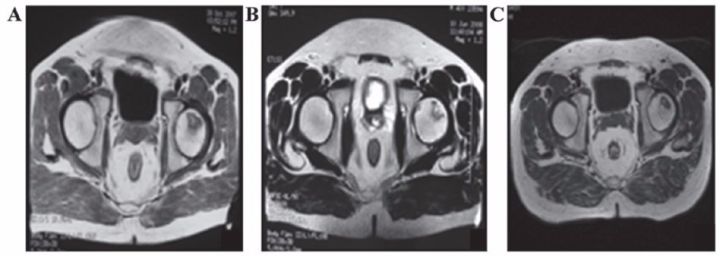

?股骨頭壞死

間充質干細胞移植治療人體股骨頭壞死在國外已有報道。法國科學家移植治療116例股骨頭壞死患者效果顯著,其中87.3%的患者髖關節疼痛緩解;78.4%的患者關節功能改善;80%的患者行走間距延長。

沈陽463醫院的楊曉鳳主任將間充質干細胞經過技術處理后注入小許的股骨頭,兩周后小許就可以下地行走了。10個月后,小許來醫院復查,他的股骨頭周圍已長出豐富的血管,表明移植的間充質干細胞促使壞死變性的股骨頭修復新生。

表8 劉穎、谷涌泉應用臍帶MSC治療股骨頭壞死的臨床研究結果

吉林省組織工程重點實驗室劉穎教授 、首都醫科大學宣武醫院谷涌泉主任等,對9位骨循環協會評級為II-IIIa級的股骨頭壞死患者經大腿動脈輸注臍帶間充質干細胞后,患者的紅細胞、血小板、血氧轉運指數明顯改善。MRI檢測顯示24個月后股骨頭壞死區域體積顯著減少。